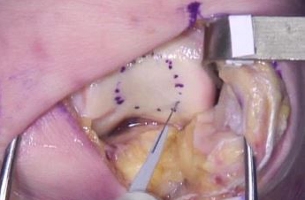

Placement of Cartiform

Four months after cartiform to femoral condyle